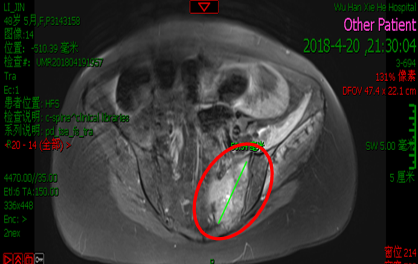

影像学检查:

2018.04